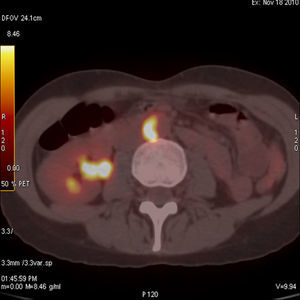

Caso clínico 2Mujer de 74 años con dolor y debilidad en cintura escapular y pelviana, con rigidez matutina de más de una hora de duración y elevación de los reactantes de fase aguda. Ante la sospecha de polimialgia reumática (PR) se administraron glucocorticoides a dosis de 30mg/día de prednisona con mejoría inicial, pero con rápida recurrencia de los síntomas y con deterioro analítico en el que destacaba una hemoglobina de 8mg/dl, PCR de 19mg/dl y VSG de 120mm en la primera hora. La paciente no refería clínica local craneal como cefalea, claudicación mandibular o dolor a la palpación de la arteria temporal y los pulsos periféricos eran normales. Ante la sospecha de neoplasia se realizó analítica con marcadores tumorales, TAC toracoabdominal, gastroscopia y colonoscopia, todo ello con resultados normales, se completó el estudio, finalmente, con la realización de un PET-TAC (fig. 2) que informó de proceso vasculítico en Ao, tronco braquiocefálico, carótidas y subclavia. Ante la firme sospecha de ACG se realizó biopsia de arteria temporal no guiada por ecografía, que confirmó el diagnóstico.